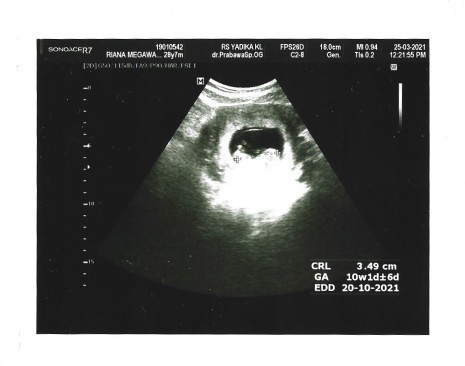

Saya menikah tahun 2018 dan selama hampir 3 tahun pernikahan belum juga dikarunia keturunan, hingga pada akhirnya bulan Februari 2021 lalu saya positif hamil. Awalnya tidak menyangka, saat ada gejala mual dan pusing saya kira itu hanya maag saja dan bahkan saya memeriksakannya ke dokter umum dan tidak ada diagnosa kehamilan dari dokter tersebut. Saya diberi obat-obatan lambung, namun 1 minggu telah berlalu tidak kunjung sembuh. Payudara saya rasanya mengencang dan akhirnya saya inisiatif untuk menggunakan testpack kehamilan karena waktu itu saya juga telat datang bulan 1 minggu dari kalender haid saya. Hasilnya garis dua! Pada saat itu saya kaget, selama hampir 3 tahun ini saya sudah mencoba puluhan testpack yang berujung hasil negatif 😖jadi sedikit ragu menggunakannya, karena tidak percaya saya mencoba lagi dengan 3 testpack dan semua hasilnya positif! Saya beritau suami saya dan betapa senangnya ia setelah menunggu selama ini. Keesokan harinya kami memutuskan mendatangi Dokter Obgyn dan dilakukan USG untuk memastikan. Alhamdulillah! Maha Besar Allah! Ternyata positif hamil dengan perkiraan usia janin 4-5 minggu walaupun pada saat itu hanya terlihat kantung saja. 1 bulan kemudian kami kembali periksa kandungan baru terlihat bentuknya dan sekarang usia kehamilan saya sudah masuk 6 bulan. Semangat untuk semua teman-teman pejuang garis dua di luar sana. Tidak ada yang mustahil apabila Tuhan berkehendak. Jangan putus berdoa, jangan putus berharap, dan perbanyak sedekah. Semoga dipermudahkan untuk kalian semua dan bagi yang sedang hamil semoga diberi kesehatan serta kelancaran untuk kita semua. #CeritaKehamilanTAP #pejuang_garisDua #firstbaby